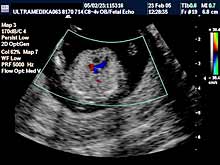

B) II trimestar trudnoće

od 16 do 24

nedelje gestacije

(4 - 6 meseca):

- SKRINING NA ANATOMSKE ANOMALIJE:

- registrovanje i procena

ultrazvučnih markera koji ukazuju na postojanje adekvatno završenog

formiranja organa ploda (embriogeneze).

Većina plodova sa poremećenom embriogenezom i postojanjem anatomskih anomalija (mozga, kičme, srca,

pluća, organa stomaka, prednjeg trbušnog zida,udova itd) se može

otkriti jedino ultrazvukom.

Radi adekvatne procene postojanja anatomskih anomalija pored Broadband

2D se koristi i 3D Sono CT i 3D CPA organskih sistema dostupnih

pregledu. 3D mekih tkiva lica je sastavni deo ultrazvučnog pregleda u

ovoj gestacionoj starosti. c)

Dopuna SKRININGA NA ANATOMSKE ANOMALIJE od

18-24. nedelje je

obavezan deo u otkrivanju urođenih anomalija ploda.

Primenjena tehnika:

- Broadband 2D,

- Sono CT,

- XRes,

- Harmonik mod,

- Panorama mod,

- 3D Sono CT,

- Broadband CD,

- CPA,

- 3D CPA.